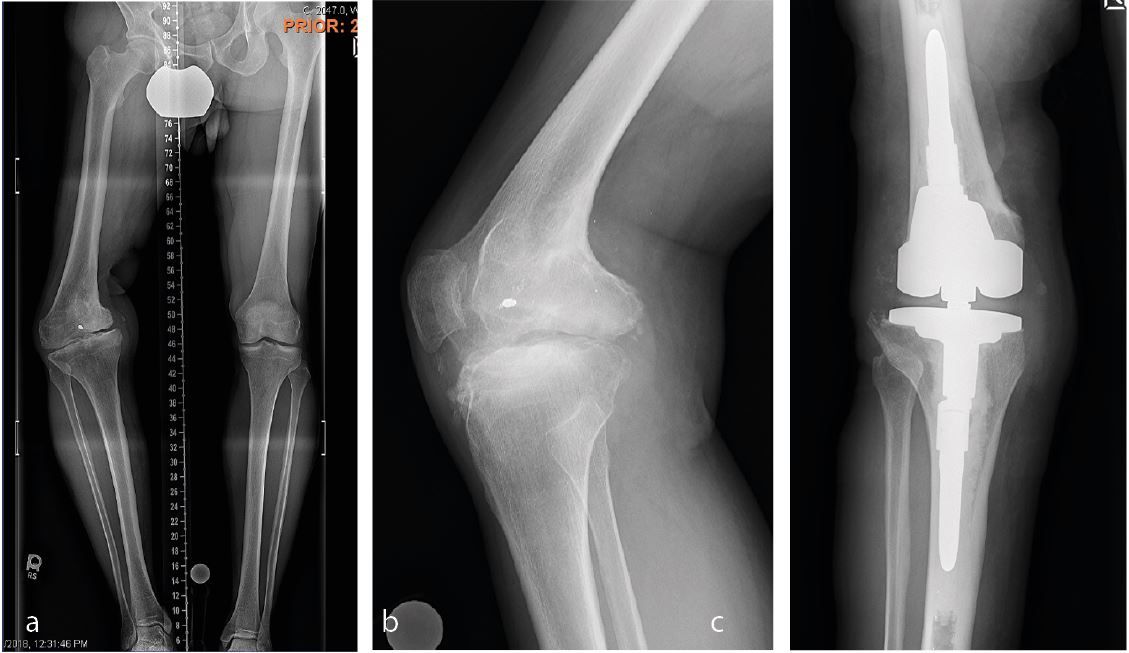

To make the decision, whether to correct the coronal deformity in a one stage or two stage fashion or to proceed with a primary total knee replacement the amount of angular deformity at the level of the knee provides the most reliable guidance. No matter where the extraarticular deformity is located doe the purpose of knee arthroplasty the overall mechanical deformity is measured as an angle between the mechanical axis of the femur (line through the center of the hip and the center of the distal femoral condyles) and the mechanical axis of the tibia (line through the center of the talus (ankle) and the center of the tibial plateau). A mechanical deformity in excess of 20-25 degrees usually suggests that a primary knee replacement without deformity correction is not possible. In these cases usually the deformity needs to be corrected first. For the correction of extraarticular deformities different options including correction over a nail, open osteotomy with plate fixation or external fixator exist. In my opinion the technique that interferes the least with the later total knee replacement should be favored. Open ostoeotomies and plate fixation should take into consideration the potential need for hardware removal at the time of surgery and plates should be placed medial along the standard medial parapatellar approach as often as possible. Correction using an intramedullary nail need to make sure that the nail does not extend into the bed of the primary knee implants and options for extramedullary alignment need to be available at the time of total knee arthroplasty (navigation, robotic or extramedullary alignment jigs) [3]. Finally, when using an external fixator, the risk of pin tract infection and osteomyelitis needs to be carefully weighed versus the ability for advanced 3-dimensional correction of the deformity. I personally had very good results with 2 stage correction using an external fixator or one stage correction using either an open plate fixation or intramedullary fixation using the stem of a revision femoral or tibial component. The later is especially appealing if the center of rotation and angulation (CORA) is close to the knee. Bony correction of the preexisting deformity renders the soft tissue balancing at the time of total knee replacement much easier and is usually indicated for less experienced surgeons. Rule of Thumb: For me a coronal deformity exceeding 25 degrees is an absolute and a deformity exceeding 20 degrees is a relative indication for a one stage or two stage correction of a preexisting extraarticular deformity (Figure 1a, b, c).

Often the first question is whether or not to remove preexisting hardware at the time of surgery or two-stage prior to knee replacement. Although there have been reports of positive cultures when evaluating removed hardware, I don’t think that prior hardware always needs to be removed before attempting a total knee replacement. Medial hardware on the proximal tibia or distal femur can usually be removed without difficulty through a standard medial parapatellar approach at the time of total knee replacement (Figure 6a, b).